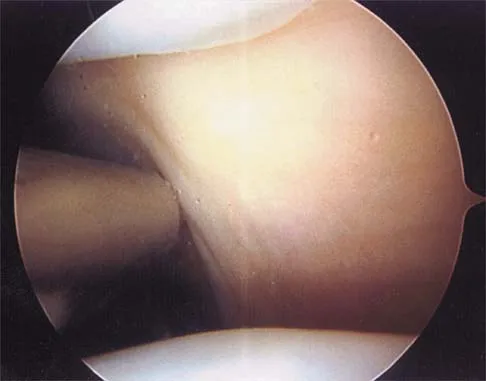

A patient has right shoulder pain. Figure 1a shows a gadolinium-enhanced transverse MRI scan at the level of the coracoid. Figure 1b shows an arthroscopic view of the anterior structures from a posterior portal. These images reveal which of the following findings?

The area shown in the arthroscopic view and MRI scan is referred to as a Buford complex and represents a normal labral variant. It consists of a thickened, cord-like middle glenohumeral ligament, a superior labral attachment of the middle glenohumeral ligament just anterior to the biceps tendon, and absence of the anterosuperior labrum. This combination of findings can be confusing and may simulate labral pathology. Mistaken repair of the lesion back to the glenoid rim can result in significant loss of external rotation. A Bankart lesion would be located at the inferior anterior glenoid rim. The subscapularis is seen anterior to the labrum. Normal variations that occur in the anterosuperior labrum can simulate pathology. Gusmer PB, Potter HG, Schatz JA, et al: Labral injuries: Accuracy of detection with unenhanced MR imaging of the shoulder. Radiology 1996;200:519-524. Griffin LY (ed): Orthopaedic Knowledge Update: Sports Medicine. Rosemont, IL, American Academy of Orthopaedic Surgeons, 1994, pp 47-63.

- Williams MM, Snyder SJ, Buford D Jr: The Buford complex: The "cord-like" middle glenohumeral ligament and absent anterosuperior labrum complex. A normal anatomic capsulolabral variant. Arthroscopy 1994;10:241-247.